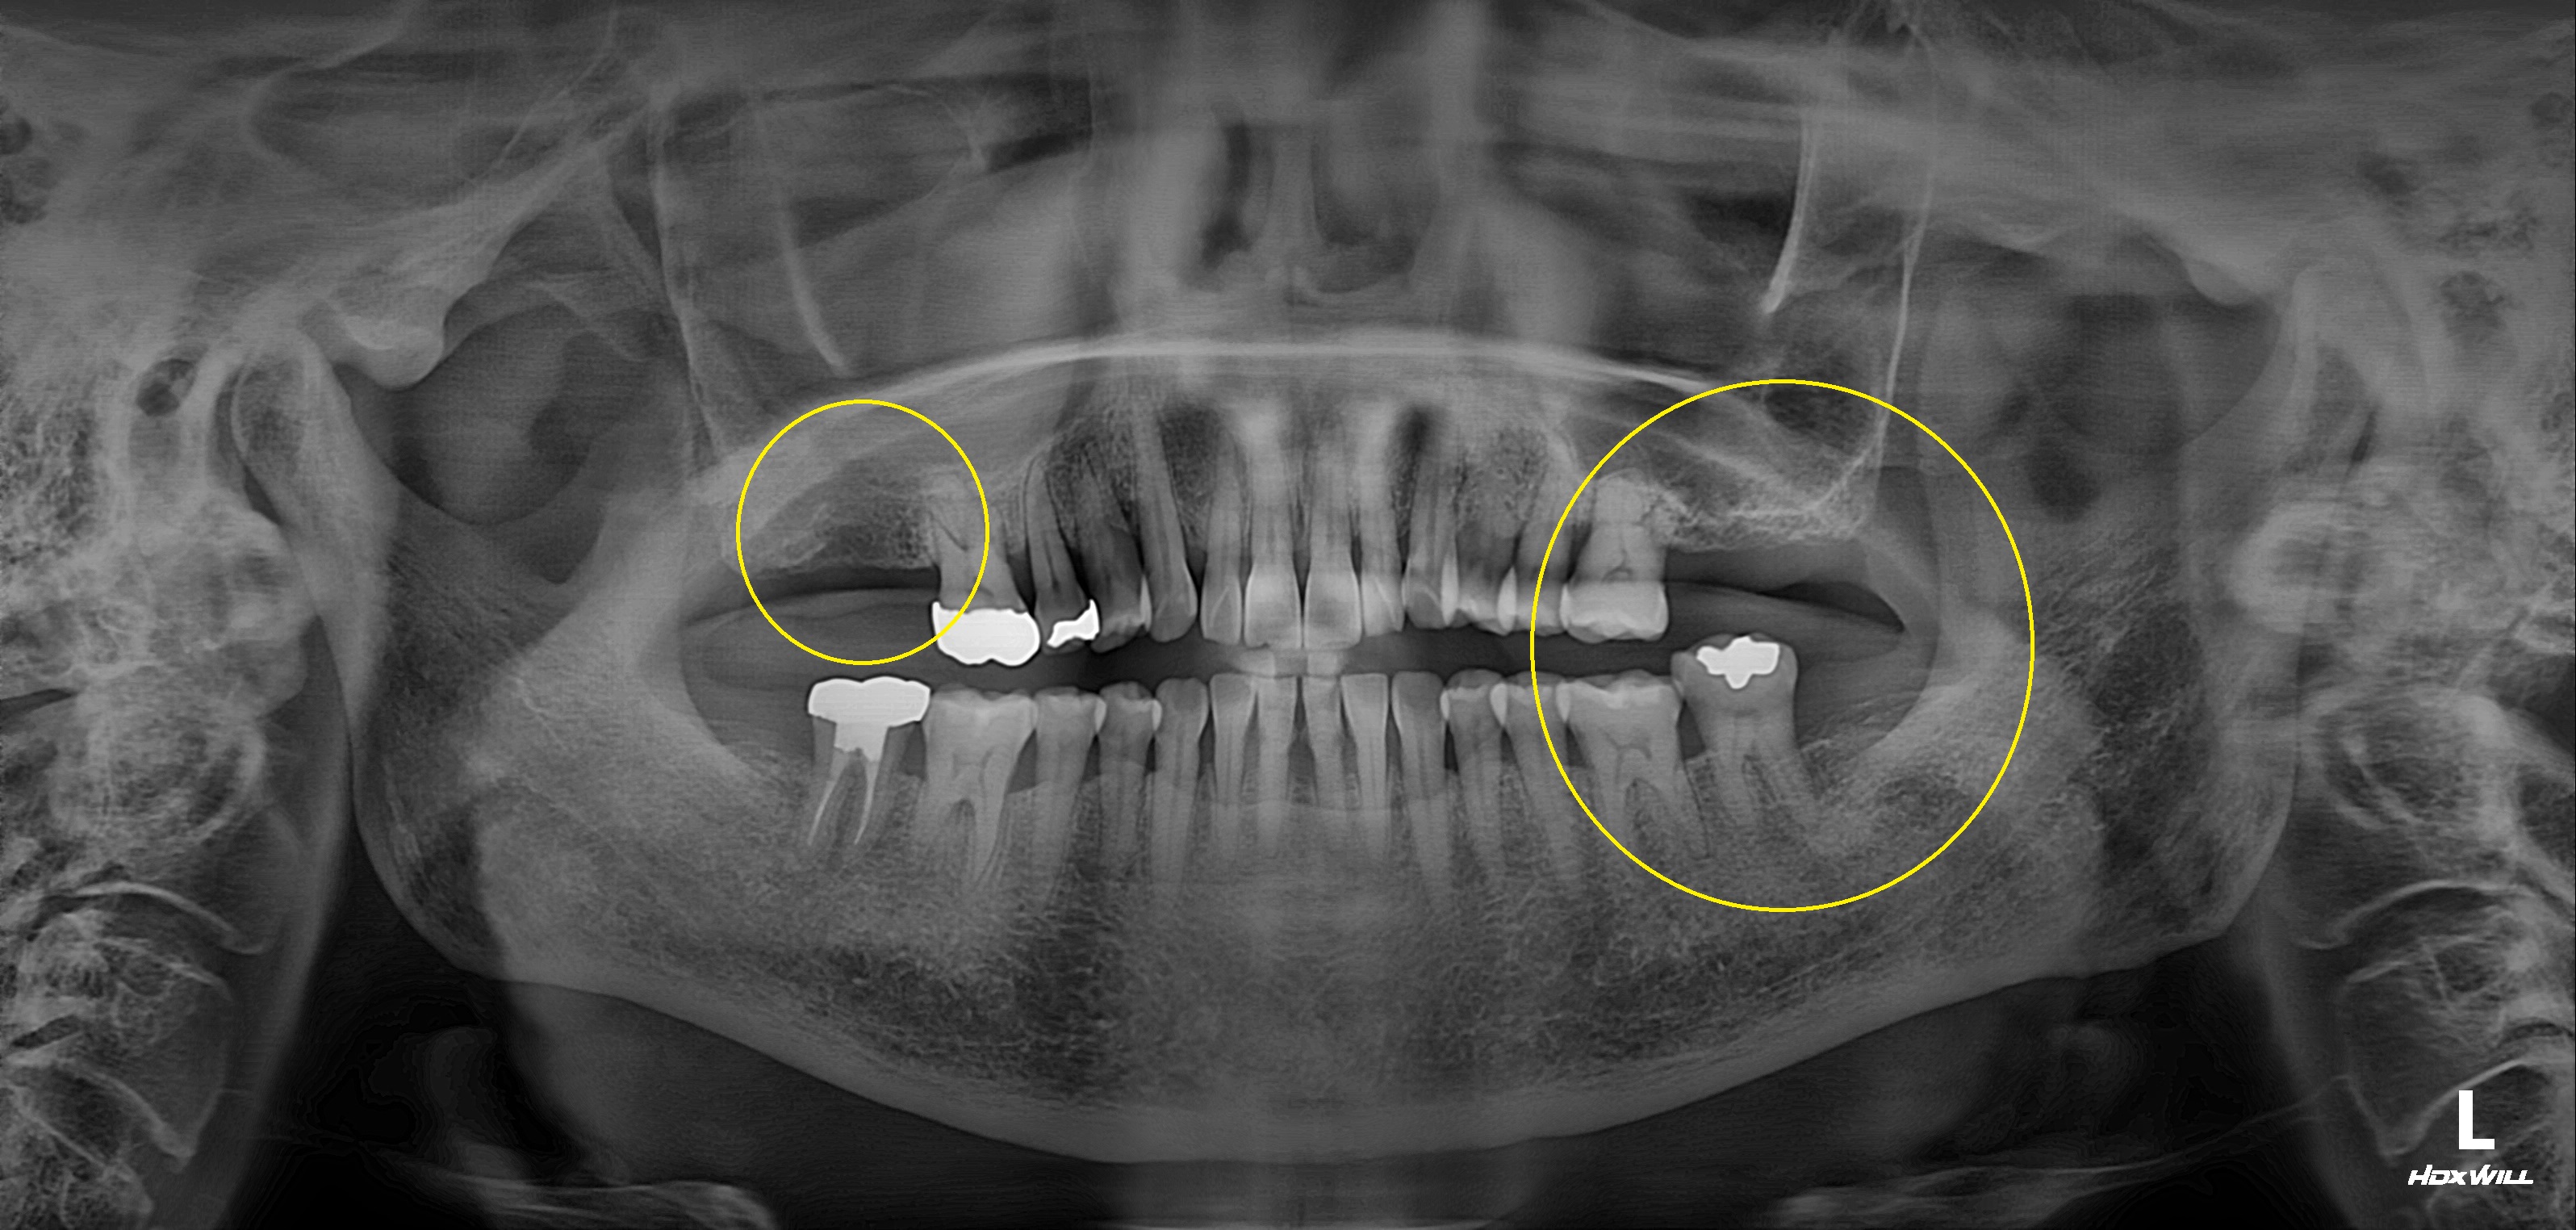

수술 전

수술 후

상악 임플란트 식립사례

전후사진